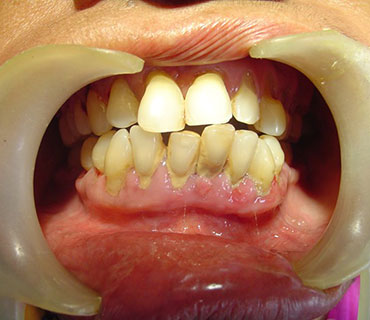

الوقاية عن طريق الفم

تشير الوقاية الفموية إلى إجراء تنظيف الأسنان الاحترافي الذي يقوم به طبيب الأسنان أو أخصائي صحة الأسنان

- يمنع أمراض اللثة

- يمنع تسوس الأسنان

- يحافظ على رائحة الفم المنعشة

- الفوائد الجمالية

- الصحة العامة